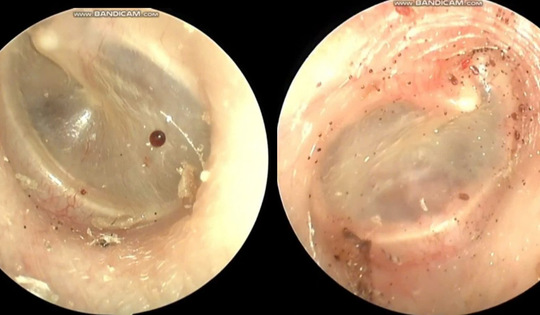

Cháu bé đau tai dữ dội, bác sĩ sốc ngang phát hiện bí mật "đáng sợ" bên trong